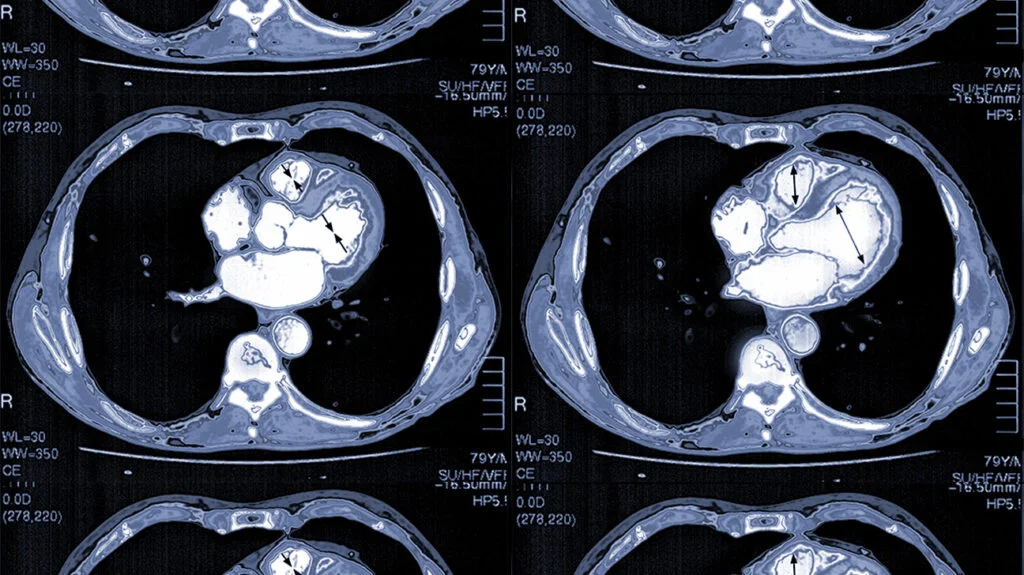

Four consecutive CT scan images of the chest showing cross-sections of the heart and surrounding structures with highlighted areas.